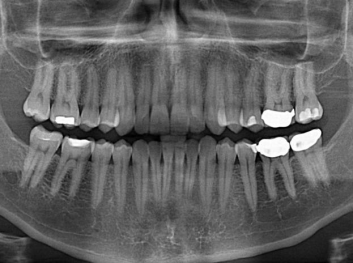

在體外測試中,材料刺激干細(xì)胞進(jìn)入牙本質(zhì)的增殖和分化速度,促進(jìn)形成牙齒骨組織。研究人員認(rèn)為,一旦材料在受損牙齒中應(yīng)用,這些干細(xì)胞可以自動修復(fù)來自填充物上的損壞。在本質(zhì)上,該生物材料將使牙齒自愈。

在未來,Adam Celiz說,可再生材料能制成各種填充物以便受損牙齒的自身治愈,降低補牙失敗率,甚至?xí)蟛糠秩藢Ω苤委煹男枰?/p>